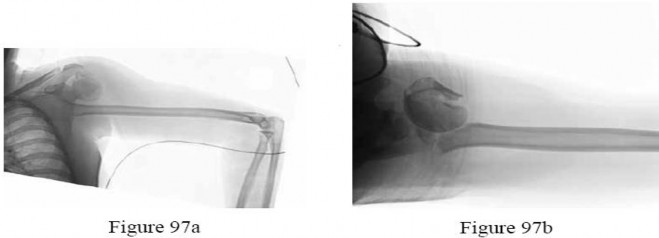

Question 14:

A 22-year-old football player sustains a recurrent anterior shoulder dislocation. An MRI arthrogram reveals a Bankart tear and a large Hill-Sachs lesion that engages the anterior glenoid rim. What is the best surgical option to address the engaging Hill-Sachs lesion?

Correct Answer: Remplissage procedure with Bankart repair

Explanation:

An engaging Hill-Sachs lesion is a defect on the posterolateral humeral head that engages the anterior glenoid during abduction and external rotation, predisposing to recurrent dislocation. The Remplissage procedure (infilling the defect with the infraspinatus tendon and capsule) combined with a Bankart repair is an effective treatment.